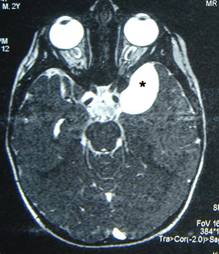

Kafa içindeki araknoid kistlerin yaklaşık yarısı beyinin şakak (temporal) bölgesinde görülür Bu bölgedeki araknoid kistler sağa oranla 3-4 kat daha fazla olmak üzere sol tarafta yerleşim gösterirler. İtalyan beyin cerrahı Galassi tarafından 3 tipe ayrılmışlardır. Tip I en küçük olanıdır ve beynin şakak bölgesinin ön kısmında iğ şeklindedir (Resim 1). Bu tiplerde genellikle herhangi bir tedavi gerekmez.

Resim 1: MRG’de şakak bölgesinde Tip I araknoid kist (*).

Dikdörtgen şeklindeki kistler de Tip II olarak sınıflandırılmıştır (Resim 2). Bu tip kistlerde tedavi yöntemi cerrahi girişimdir. Tip III kist ise en büyük olanıdır. Kist şakak bölgesinden

Resim 2: MRG’de beynin şakak bölgesinde beyin şakak bölümünü geriye doğru iten Tip II araknoid kist görülmektedir.

beyinin üst kısmına doğru yayılım görülür. Beyin orta hat yapılarında karşı tarafa doğru itilmelere neden olur (Resim 3).

Resim 3: BT de Tip III temporal araknoid kist ve beynin orta hattaki yapılarında karşı tarafa itilme izlenmektedir.